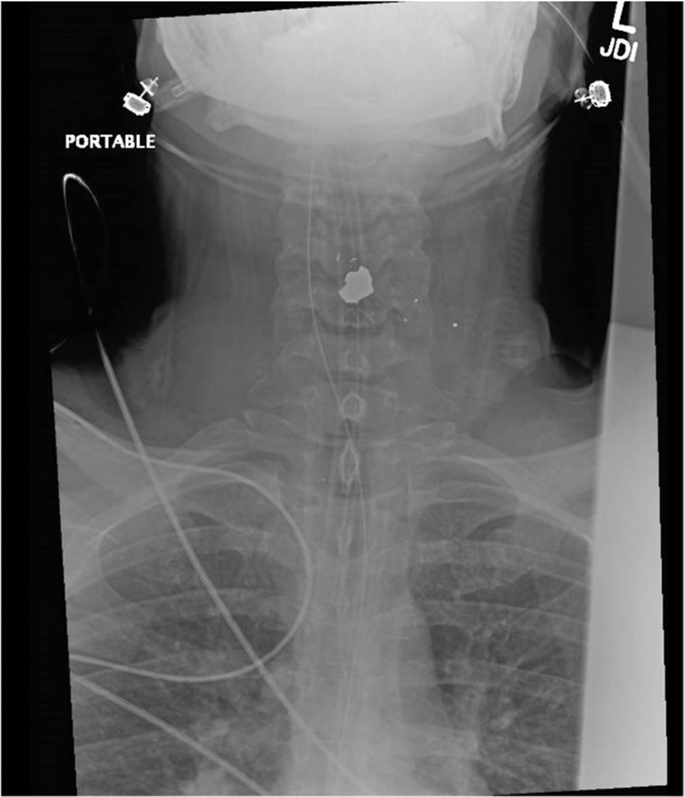

Anonymous (ID: BsS2pIST) United States No.515389910 >>515392352 >>515395828 >>515397804 >>515400298 >>515400950 >>515405390 >>515406513 >>515412573

Top 1% spatial I.Q. here. I know you faggots think the bullet came from above, but you're fucking wrong.

The bullet is coming from below, possibly very close nearby. You can see where Charlie's 5'clock shadow starts and compare it to the where the bullet hits and where his shirt is sitting. The bullet (I believe) comes from below, hits Charlie through the collar of his shirt causing it to jump up and through his neck, finally exiting in an upward fashion from which it was shot.

>>515389910

is he wearing a vest under the shirt? Did they shoot the vest an it deflected into his neck?

100% was shot in the plate above left nipple and the spalling went up and ripped his throat out. Remember to give me (you)s when I'm vindicated.

Anonymous (ID: FE4pLHym) Australia No.515400950 >>515405506

To go up it would have to be incredibly close range. The crowd's reaction was clearly to a distant sniper shot, not someone shooting from among them. Also, from the size of that hole and from close range, the whole back of his neck/head should have exploded.

Makes more sense what people are saying, it was from up high, caught the top half of his vest and then a large bullet fragment, already greatly slowed down, entered his neck causing catastrophic arterial damage.

The bullet being slowed down by already having hit a ballistics vest would explain why there wasn't more mess. It probably entered his neck/head and just spun like a top for a couple microseconds, ensuring surviving was impossible.

I'm betting he actually got shot in the back of the head and the bullet ricocheted towards the neck

The bullet hit his bulletproof vest and ricocheted through his carotid. That's why it exits upward.

Shot hit him in the chest, defected off whatever plate or bulletproof vest he was wearing under the shirt, and then tumbling bullet ended up catching him in the neck.

This is a good theory, but the decorticate posturing necessitates that the bullet or fragment struck either his spinal cord, brainstem, or spalled into his brain.